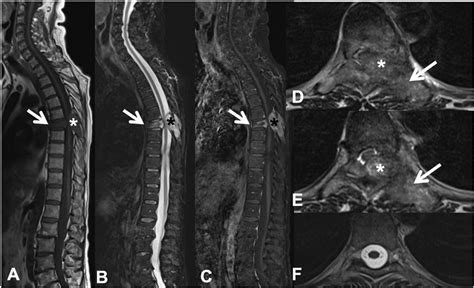

Cuando el paciente presenta una sintomatología relacionado con la columna vertebral, es importante que el especialista pregunte sobre las características del dolor que presenta el paciente. La resonancia magnética es la prueba más específica para comprobar el estado de los ligamentos amarillos de la columna vertebral. La mejor forma de diagnosticar la hipertrofia del ligamento amarillo o el engrosamiento del ligamento flavum es mediante una resonancia magnética de la columna vertebral.

Resonancia Magnética de la Columna Vertebral